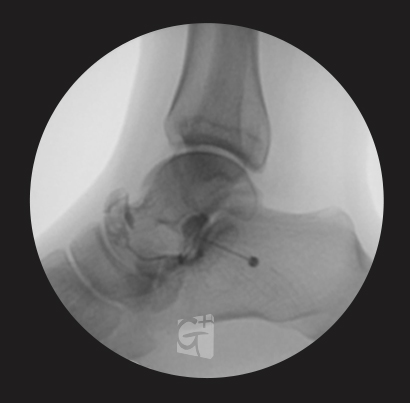

발목 치료1

거골-종골 관절염 등

염증 부위에 주사 시술 -